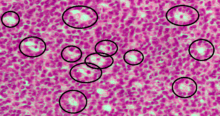

Call–Exner bodies marked with black circles in an intermediate-high magnification micrograph of a granulosa cell tumour, a type of sex cord stromal tumour. H&E stain.

Call–Exner bodies are small eosinophilic fluid-filled spaces between granulosa cells.[1] The granulosa cells are usually arranged haphazardly around the space.

They are pathognomonic for Granulosa cell tumors.